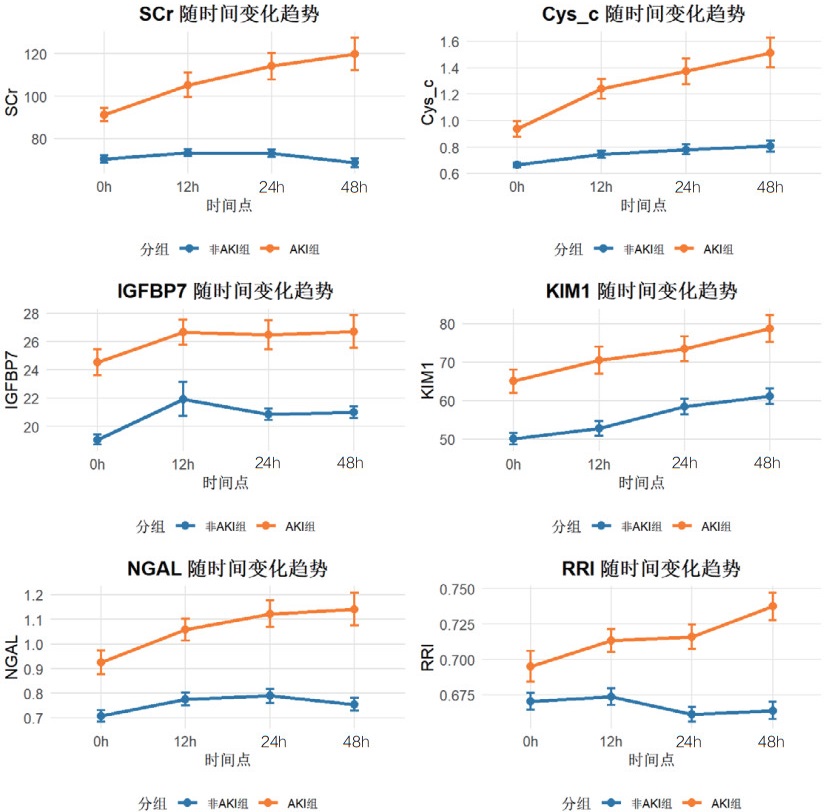

为了动态观察急性肾损伤相关生物标志物及肾阻力指数的变化,绘制了AKI组与非AKI组在0 h、12 h、24 h和48 h四个时间点的血清Cys-C、IGFBP-7、KIM-1、NGAL和超声RRI水平的变化趋势图,见图 6。动态监测显示,AKI组患者血清Cys-C、IGFBP-7、KIM-1、NGAL水平及超声RRI值在各时间点均显著高于非AKI组,且呈现不同的时间变化模式。

| 图 6 各指标随时间变化的趋势图 |

本研究结果显示,既往存在肾脏疾病是发生AKI的危险因素,AKI患者早期SCr和BUN水平显著高于非AKI组患者,AKI组患者的eGFR指标更低。其次,AKI组患者在0 h、12 h、24 h和48 h时间段内,血清NGAL、Cys-C、KIM-1、IGFBP-7水平及超声RRI值均高于非AKI组更高。这一结果提示,该生物标志物和RRI值的变化可以作为AKI早期诊断的敏感指标。此外,RRI值的升高也反映了肾脏血管阻力的增加和肾脏血流灌注的减少,是AKI发生的重要预测因素。但是单一指标的检测存在局限性,各项指标绘制的ROC曲线AUC值相对偏低,联合检测的AUC值优于各单项指标检测,其中联合检测48 h的AUC值最高为0.872(95%CI: 0.820~0.924),且敏感度和特异度相对较高。对各时间段联合检测指标显示各时间段预测性能比较接近,AUC值均大于0.8,提示联合检测稳定性和预测性能良好。此外,对各指标随时间变化的动态监测显示,Cys-C和KIM-1呈持续上升趋势,IGFBP-7在12 h达峰值后略有下降,NGAL在早期即显著升高并维持高水平,RRI随时间推移逐渐上升。这些指标的动态监测为AKI的早期识别、严重程度评估和预后判断提供了重要依据。不同指标在时间维度上的变化特征也反映了AKI发生发展过程中不同的病理生理机制。